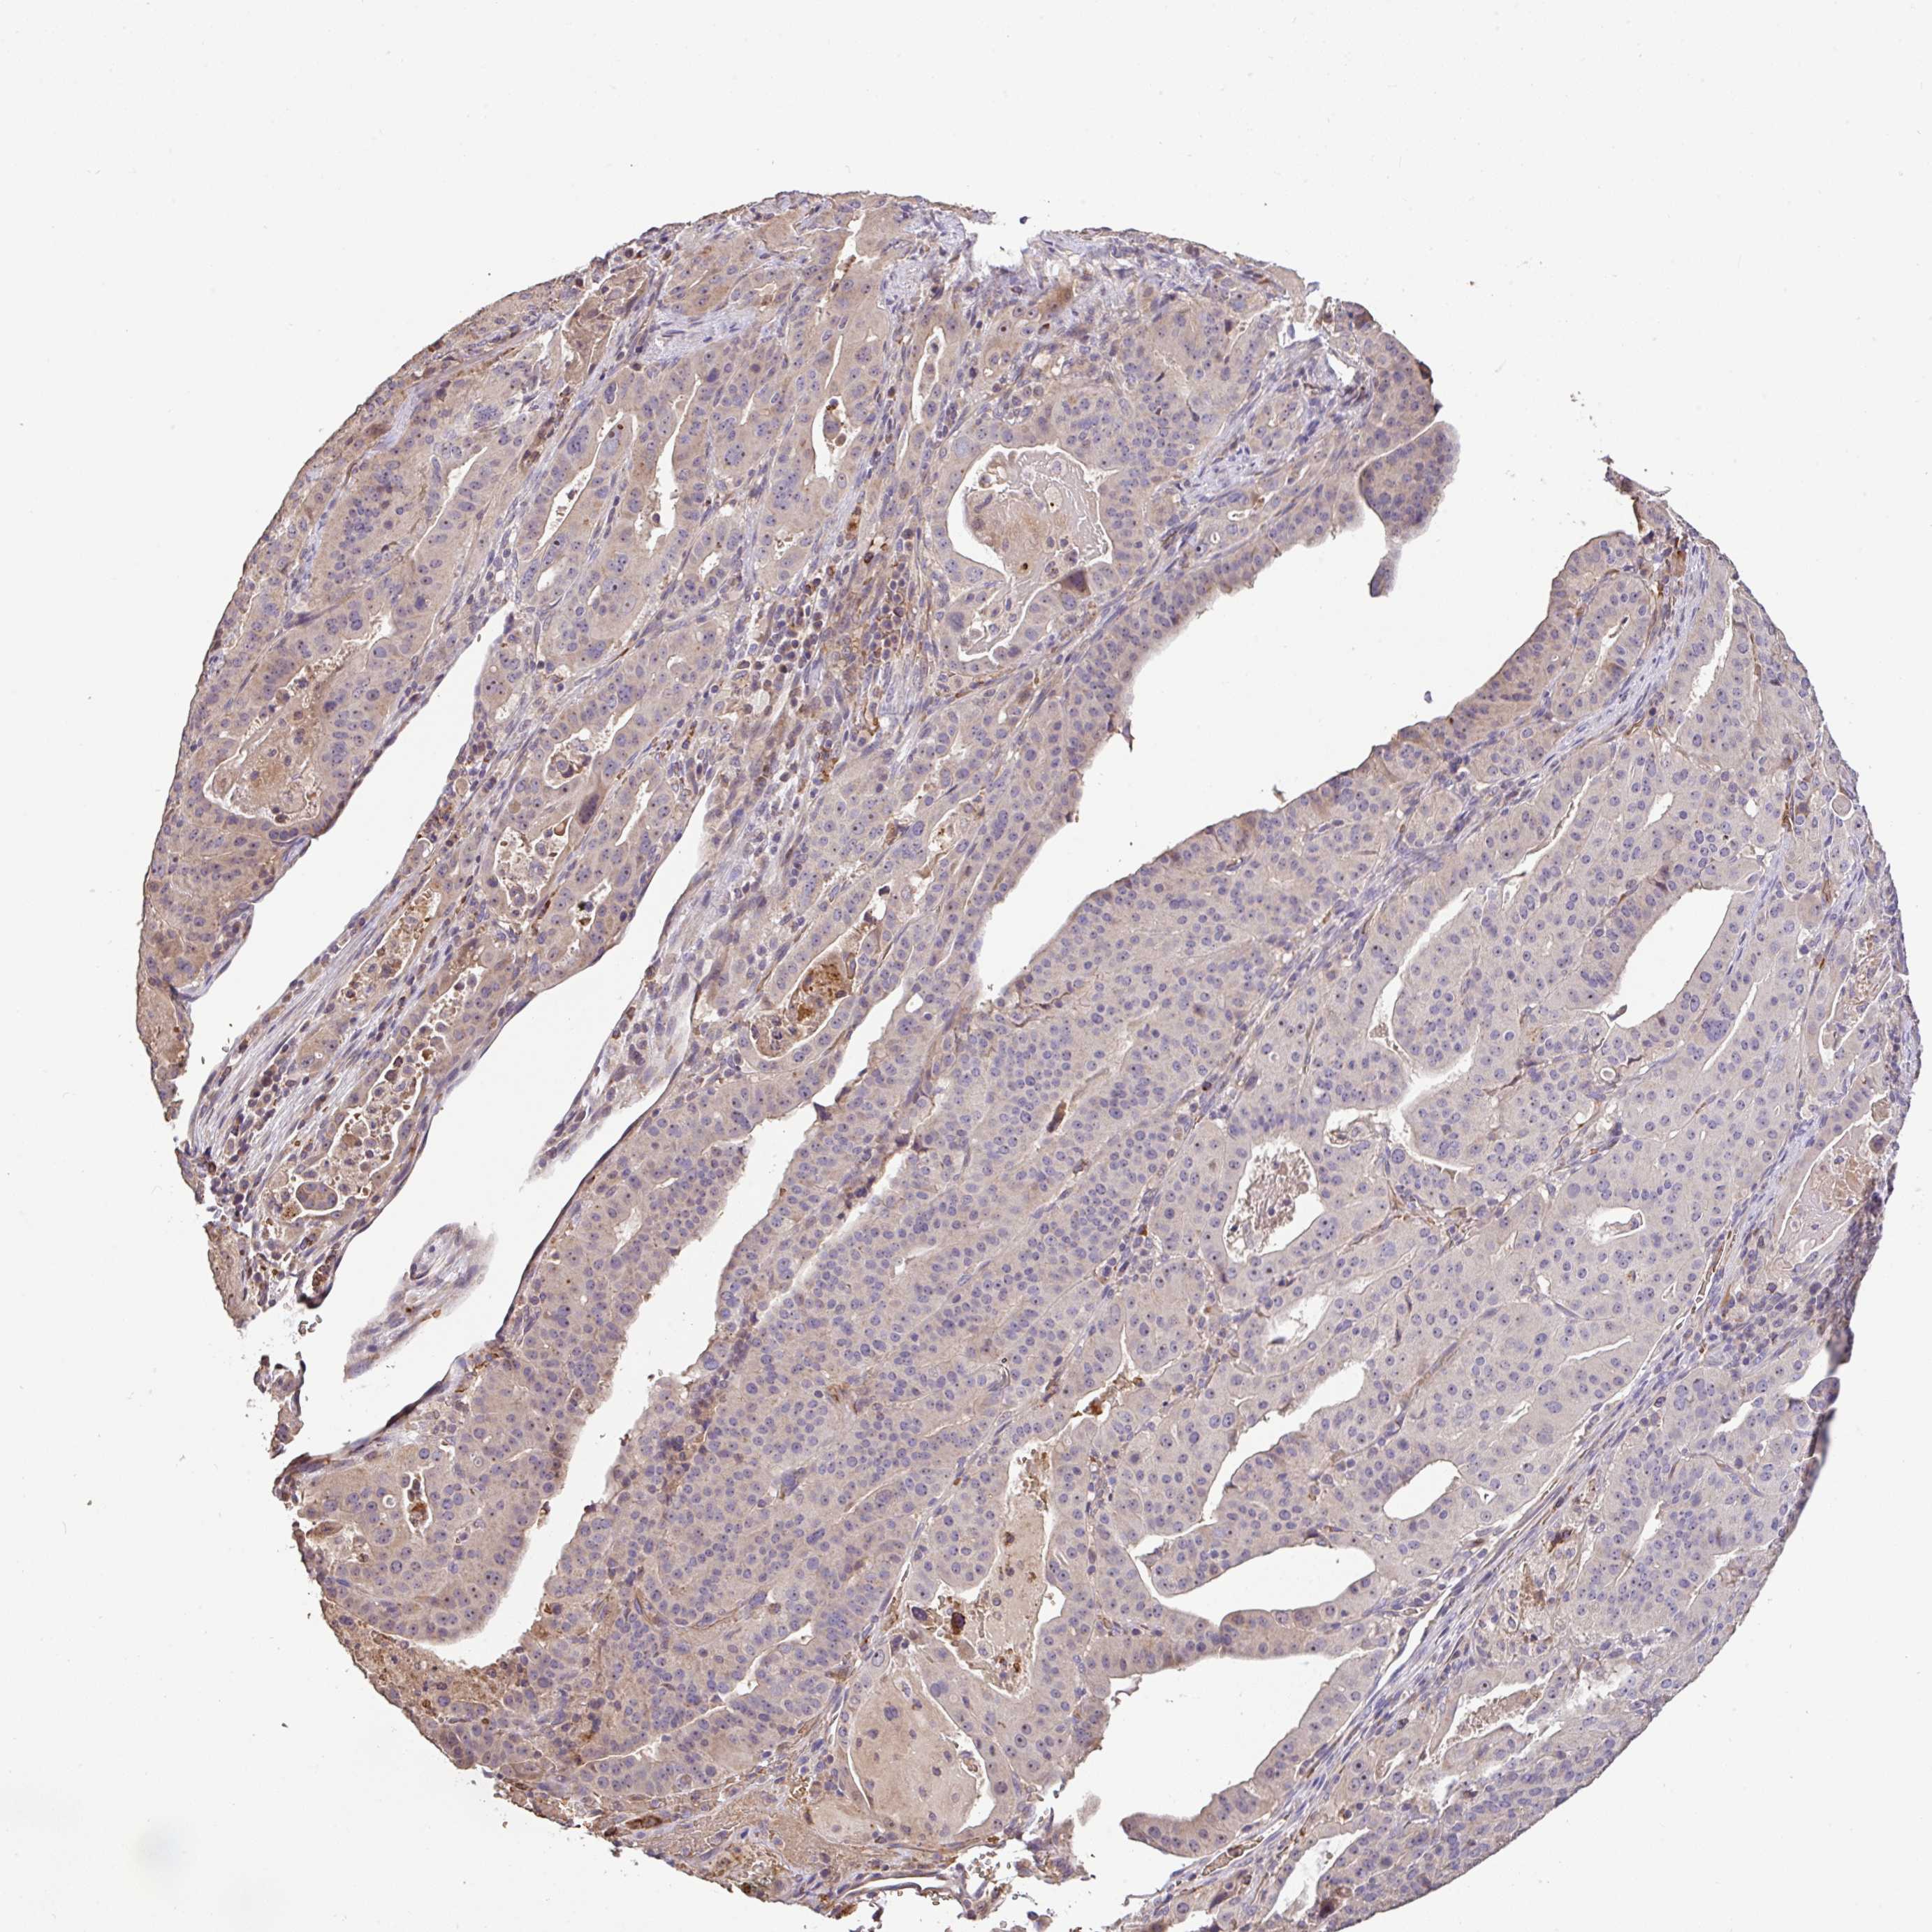

STOMACH CANCER - Protein expressioni

A mouse-over function shows sample information and annotation data. Click on an image to view it in a full screen mode. Samples can be filtered based on level of antibody staining by selecting one or several of the following categories: high, medium, low and not detected. The assay and annotation is described here.

Note that samples used for immunohistochemistry by the Human Protein Atlas do not correspond to samples in the TCGA dataset.

Antibody stainingi

Antibody staining in the annotated cell types in the current human tissue is reported as not detected, low, medium, or high, based on conventional immunohistochemistry profiling in selected tissues. This score is based on the combination of the staining intensity and fraction of stained cells.

Each image is clickable and will lead to virtual microscopy that enables deeper exploration of all samples and also displays staining intensity scores, fraction scores and subcellular localization as well as patient and tissue information for each sample.

Antibody HPA056632

Staining

High

Medium

Low

Not detected

Intensity

Strong

Moderate

Weak

Negative

Quantity

>75%

75%-25%

<25%

None

Location

Nuclear

Cytoplasmic/membranous

Cytoplasmic/membranous,nuclear

Adenocarcinoma, NOS